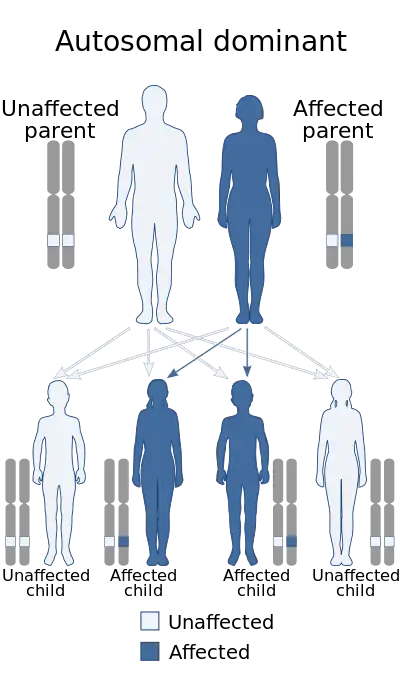

Genetic disorders can also cause endometrial cancer. Overall, hereditary causes contribute to 2–10% of endometrial cancer cases.[3][26] Lynch syndrome, an autosomal dominant genetic disorder that mainly causes colorectal cancer, also causes endometrial cancer, especially before menopause. Women with Lynch syndrome have a 40–60% risk of developing endometrial cancer, higher than their risk of developing colorectal (bowel) or ovarian cancer.[17] Ovarian and endometrial cancer develop simultaneously in 20% of people. Endometrial cancer nearly always develops before colon cancer, on average, 11 years before.[18] Carcinogenesis in Lynch syndrome comes from a mutation in MLH1 or MLH2: genes that participate in the process of mismatch repair, which allows a cell to correct mistakes in the DNA.[17] Other genes mutated in Lynch syndrome include MSH2, MSH6, and PMS2, which are also mismatch repair genes. Women with Lynch syndrome represent 2–3% of endometrial cancer cases; some sources place this as high as 5%.[18][22] Depending on the gene mutation, women with Lynch syndrome have different risks of endometrial cancer. With MLH1 mutations, the risk is 54%; with MSH2, 21%; and with MSH6, 16%.[27]